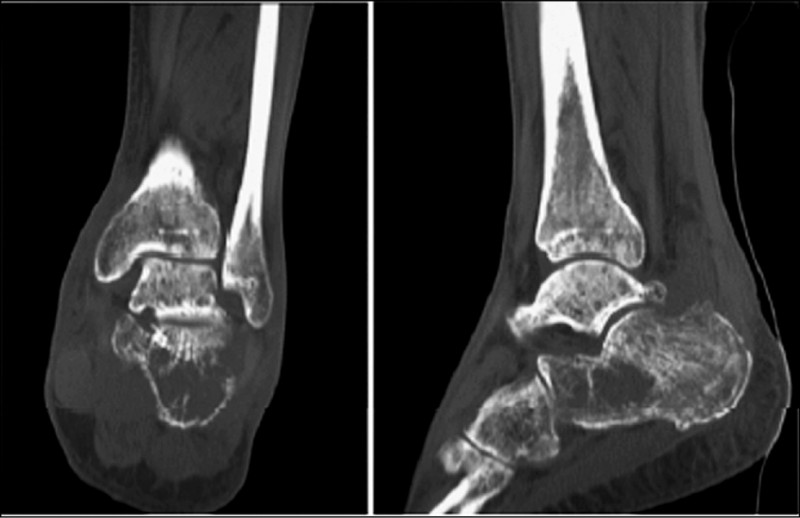

骨骼/脊椎疾病

健康網》關節卡卡不只姿勢問題! 醫點名4大護骨食物

健康網》50歲後最怕不是老 醫警:輕忽「這件事」恐讓失能提早找上門